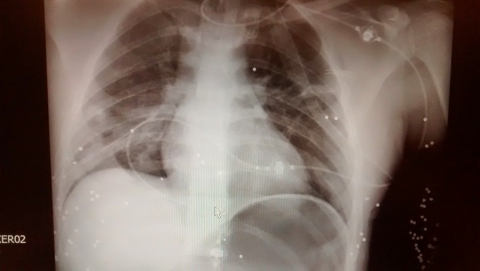

Раненого забрали от подъезда №4 дома №45 по Саратовскому шоссе. В городской больнице врачи диагностировали проникающее огнестрельное ранение грудной клетки с повреждением легкого.